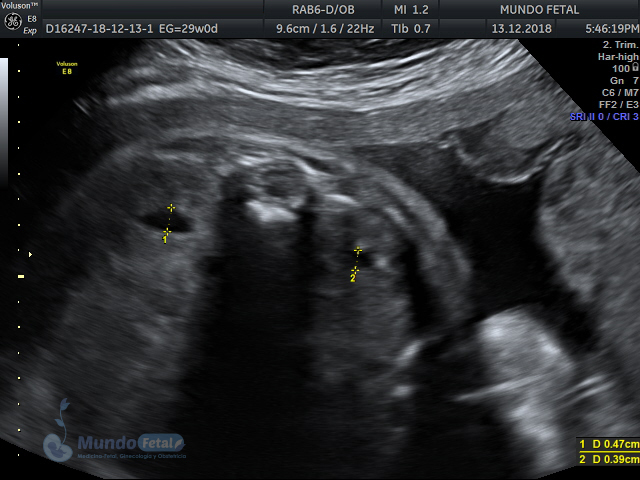

Mediante esta técnica ultrasonográfica, evaluamos en tiempo real al bebe y monitoreamos electrónicamente la frecuencia cardiaca fetal, vigilando los siguientes parámetros:

A cada parámetro se le asigna un puntaje basado en una escala del 0 al 10. Se ha propuesto que en estados fetales alterados por disminución del oxígeno se alteran los parámetros de manera que podemos predecir el estado fetal evaluando estos puntos.